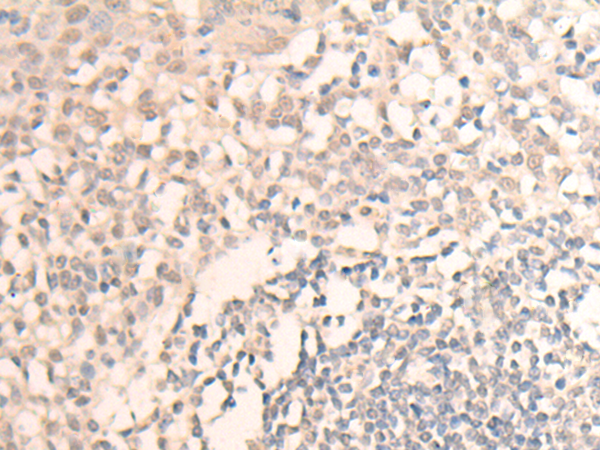

IHC positive control: |

Human tonsil |